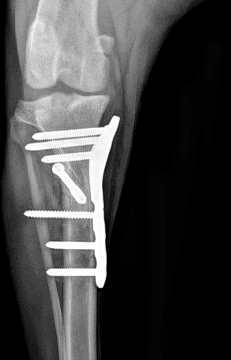

정형외과 전공의 수의사가 직접 수술합니다.

02C-arm을 통해서 좀 더 섬세한 정형외과 수술을 진행하고, 본원에서는 외과적 침습을 최소화 하는 중재적 시술 (기관 협착, 동맥관개존증(PDA), SUB 등)을 진행하고 있습니다.

12정교한 정형외과 도구를 사용하여 신속 정확한 정형외과 수술이 가능

13수술 중 골절 상태 혹은 이식물 적용 후 상태 등 육안으로 명확히 확인하기 힘든 상태를 X-ray 확인하여 정확한 수술 결과를 만들어 내는 것이 가능